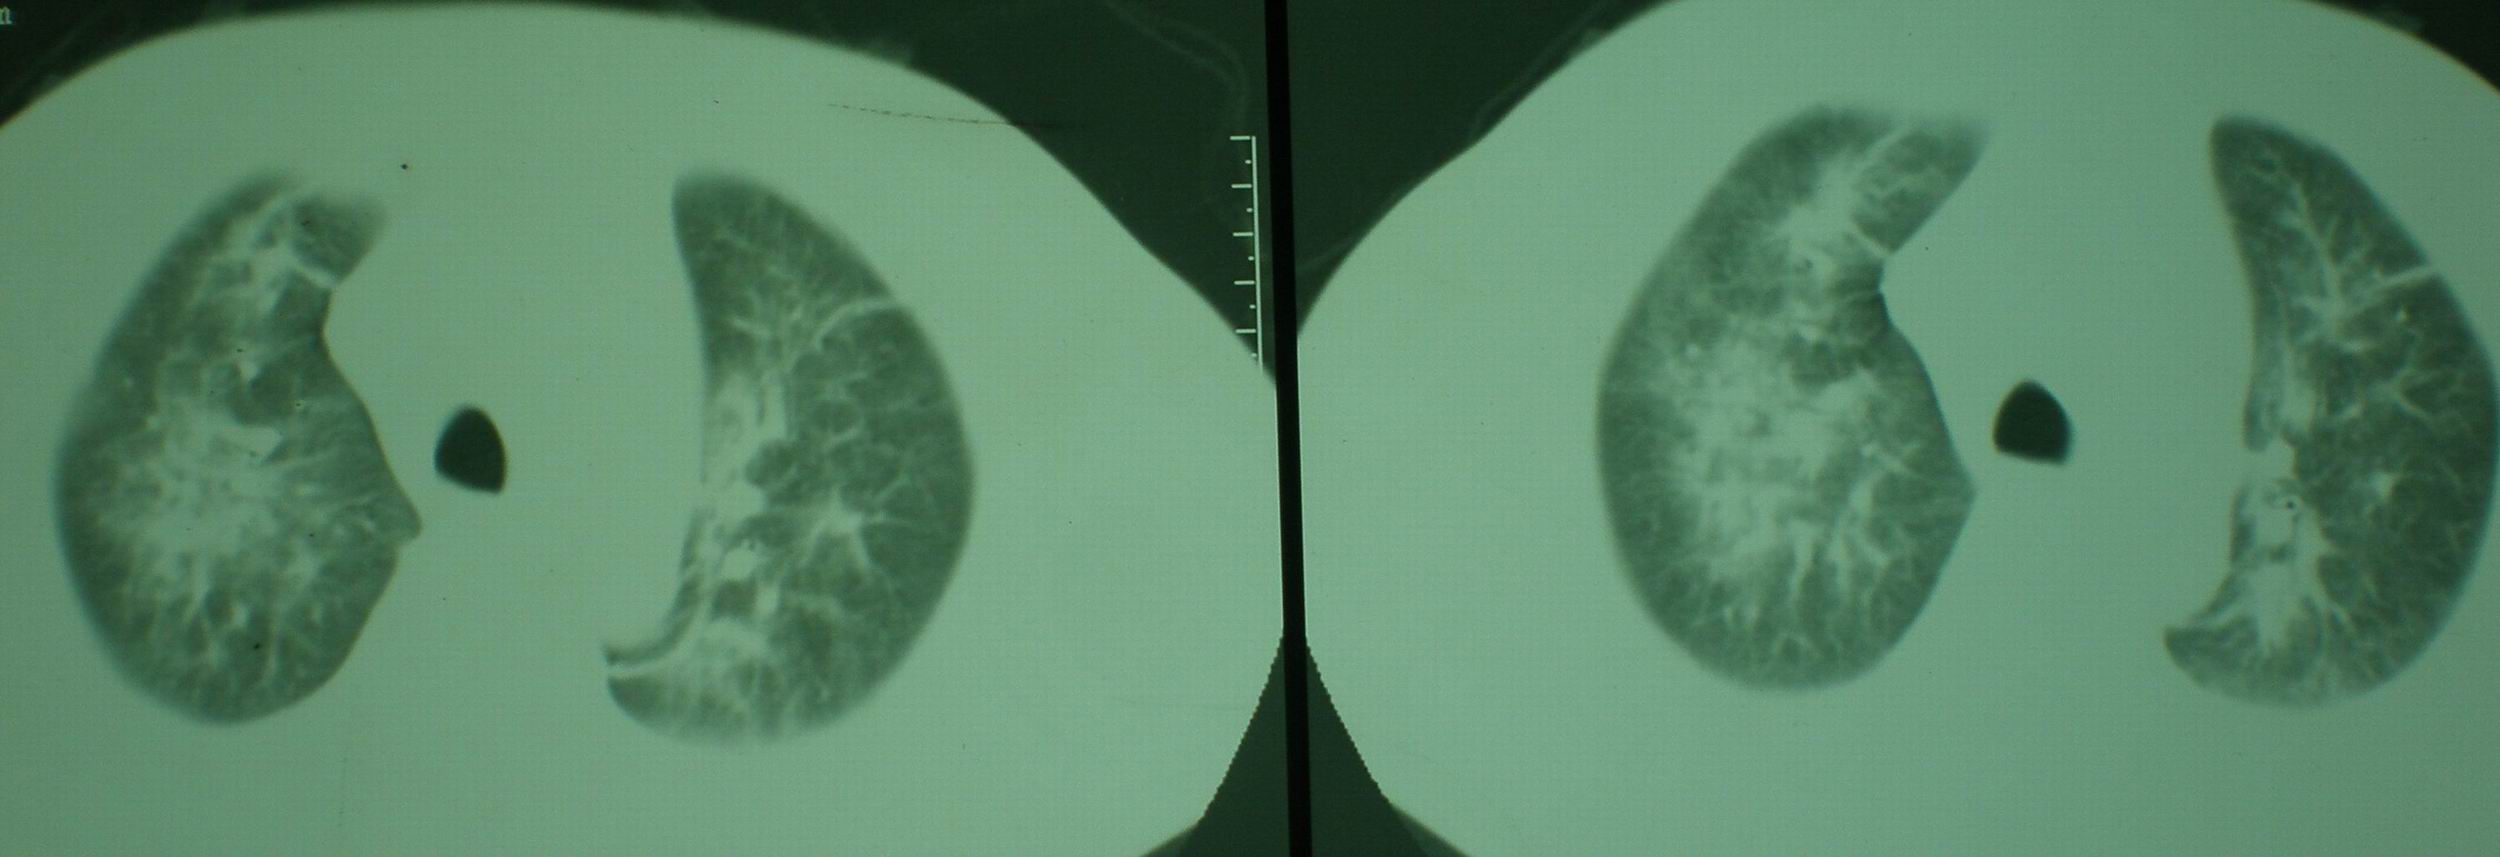

2008年11月18日今天的ct片

[face=宋体]显然上级医院进行了抗结核,抗真菌,抗炎等治疗,目前病人肺内病灶基本消失,双侧胸腔积液,右侧积液量有吸收,抗结核一个多月,现在病人疑问,结核的诊断是否有疑义,抗结核是否继续,因为那个毕竟副作用大。[/face]

机遇性感染!不除外急性肺水肿!

我仔细看了下病人的出院小结,当时情况危急,诊断里有1型呼衰。心包周围的是脂肪密度。结合三次ct扫描的图象分析,个人认为:1、病人目前肺部病灶基本消失,双侧胸腔内少量积液,抗结核治疗才一个多月,就算是结核,抗结核治疗有效果,为何效果如此好,一点纤维灶的痕迹都没有呢,再就是患者做过气管镜检查及活检、痰检均未找到结核的证据。所以不支持结核的诊断。

2、结合现在的ct片,考虑:肺水肿及真菌感染,双侧胸腔积液。

急性呼吸窘迫综合征,肺水肿,与激素减量太快有关.双侧胸腔积液.

典型的机遇性感染改变.

机遇性感染。双肺实质满布。且以肺门周围为主。不象结核。